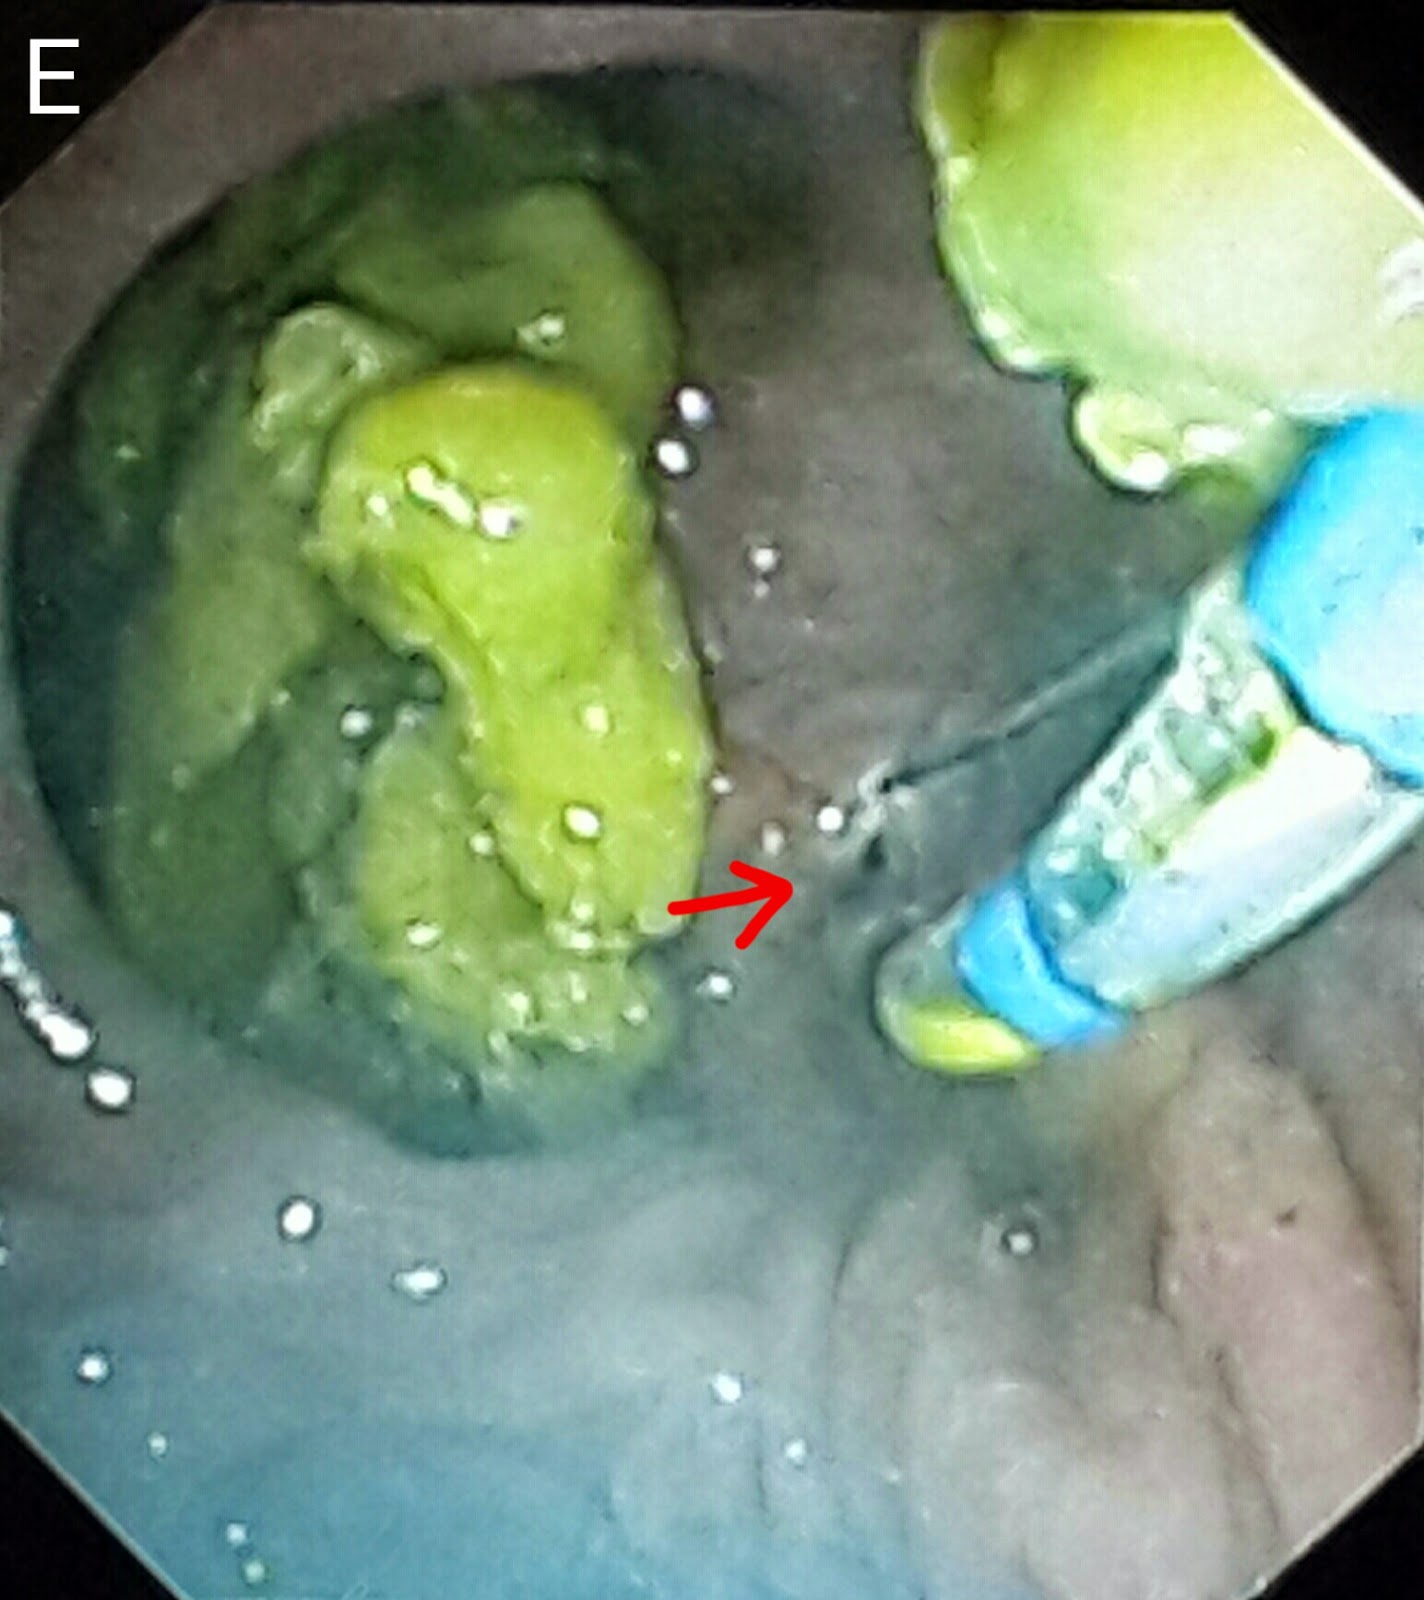

This 30 year old gentleman had developed biliary pancreatitis. He was treated at another facility a month ago where a papillotomy was done and his CBD was cleared of stones/sludge. A straight 10 French stent of 5 cm length was passed. The pancreatic duct could not be cleared at that time as duct access was unsuccessful. The patient was then referred to us. We were greeted with a post-papillotomy papillary with sign of the previous stent-it must have slipped keeping in mind the papillotomy (perhaps a pigtail stent shoulder been used). We were lucky in gaining rapid pancreatic duct access and congrats injection clearly showed two negative shadows (A: white arrows). The guidewire was then advanced further (B: red arrow) and a balloon assembly was then pushed over it (B: white arrow). The pancreatic duct was the swept with the balloon (C: white arrow shows the inflated balloon in the middle of the pancreatic duct). A lot of small white stones and sludge was removed by multiple balloon sweeps (D1 & D2: red arrows). An occlusion pancreaticogram with the balloon inflated at the distal end of the pancreatic duct (E: white arrow) showed a clear duct with no stones.

We then accessed the CBD (F: blue arrow shows the papillotome in the CBD. White arrow marks the opening of the pancreatic duct in the papilla). Contrast injection outlined a clear bile duct (G: red arrows show the bile duct. White arrows show the contrast in the pancreatic duct). The CBD was swept with balloon.